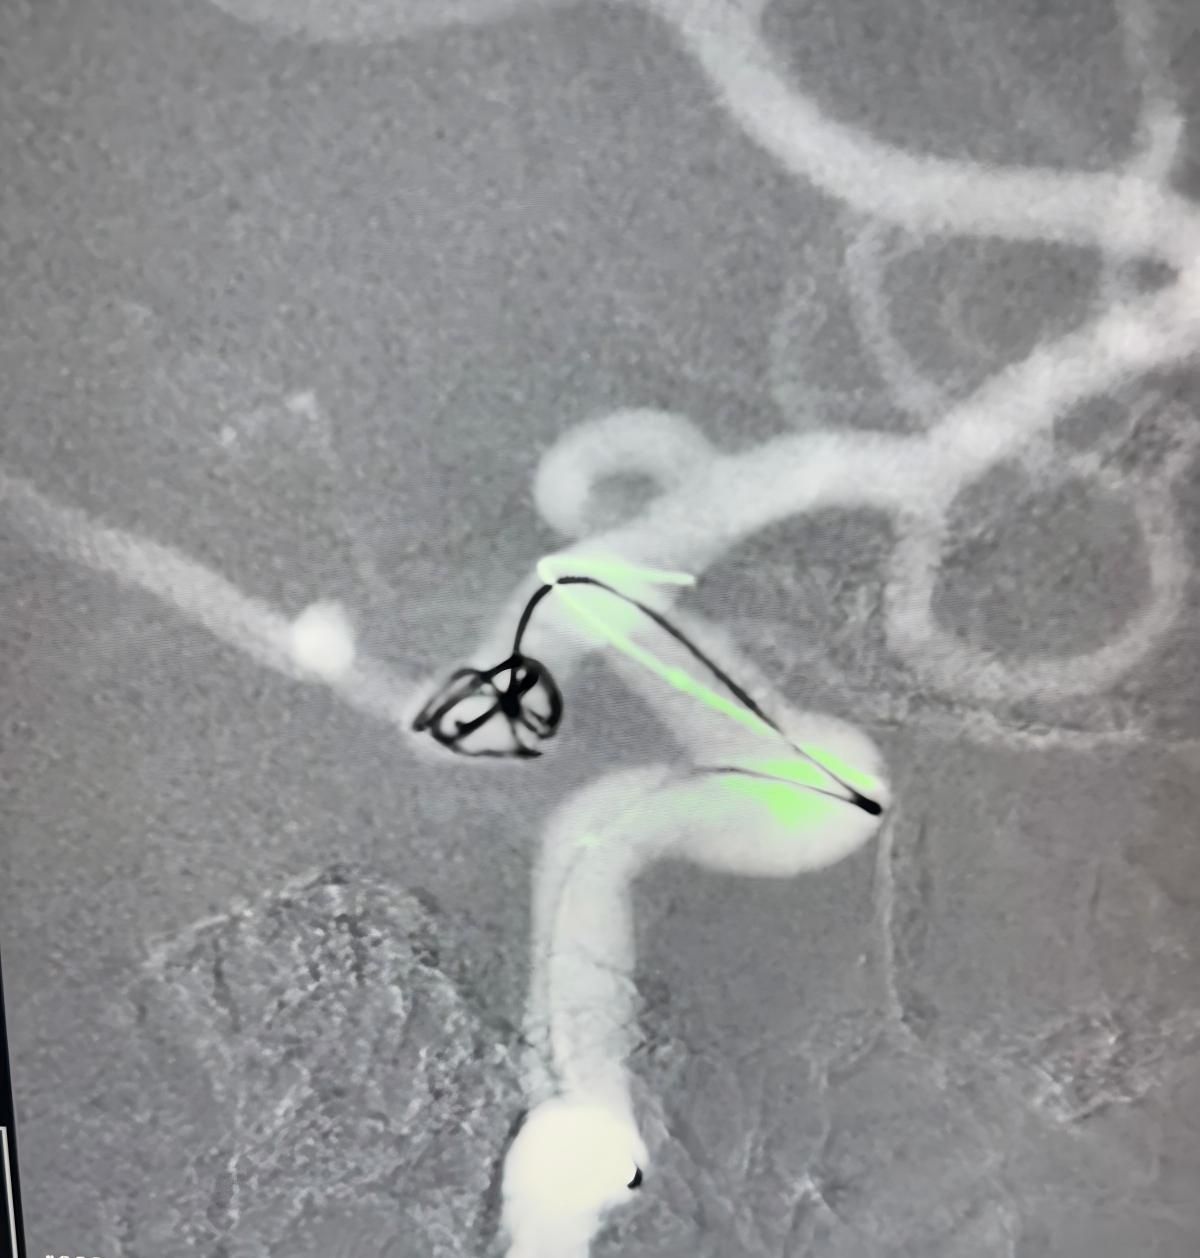

Die Behandlung nutzte die Nuva®Durchfluss-Diver ter (TJED-D 5.0-14), Perdenser®3D-Spule und Frepass®Mikro katheter (TJMC18 Plus) für ein posterior kommunizieren des Arterien aneurysma.

Dr. Mutis hob die hervorragende Sichtbarkeit des Geräts hervor und stellte fest, dass das Abrufen reibungslos verlief. Er zeigte sich sehr zufrieden mit dem Endergebnis.